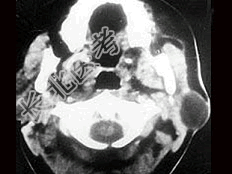

- [材料题] 女性,30岁,左侧腮腺无痛性包块5个月,无面瘫,触诊肿块质韧,表面光滑。大小约6×8厘米,B超示腮腺浅叶实性肿块 ,均质,包膜完整。患者相片及影像资料见下图。